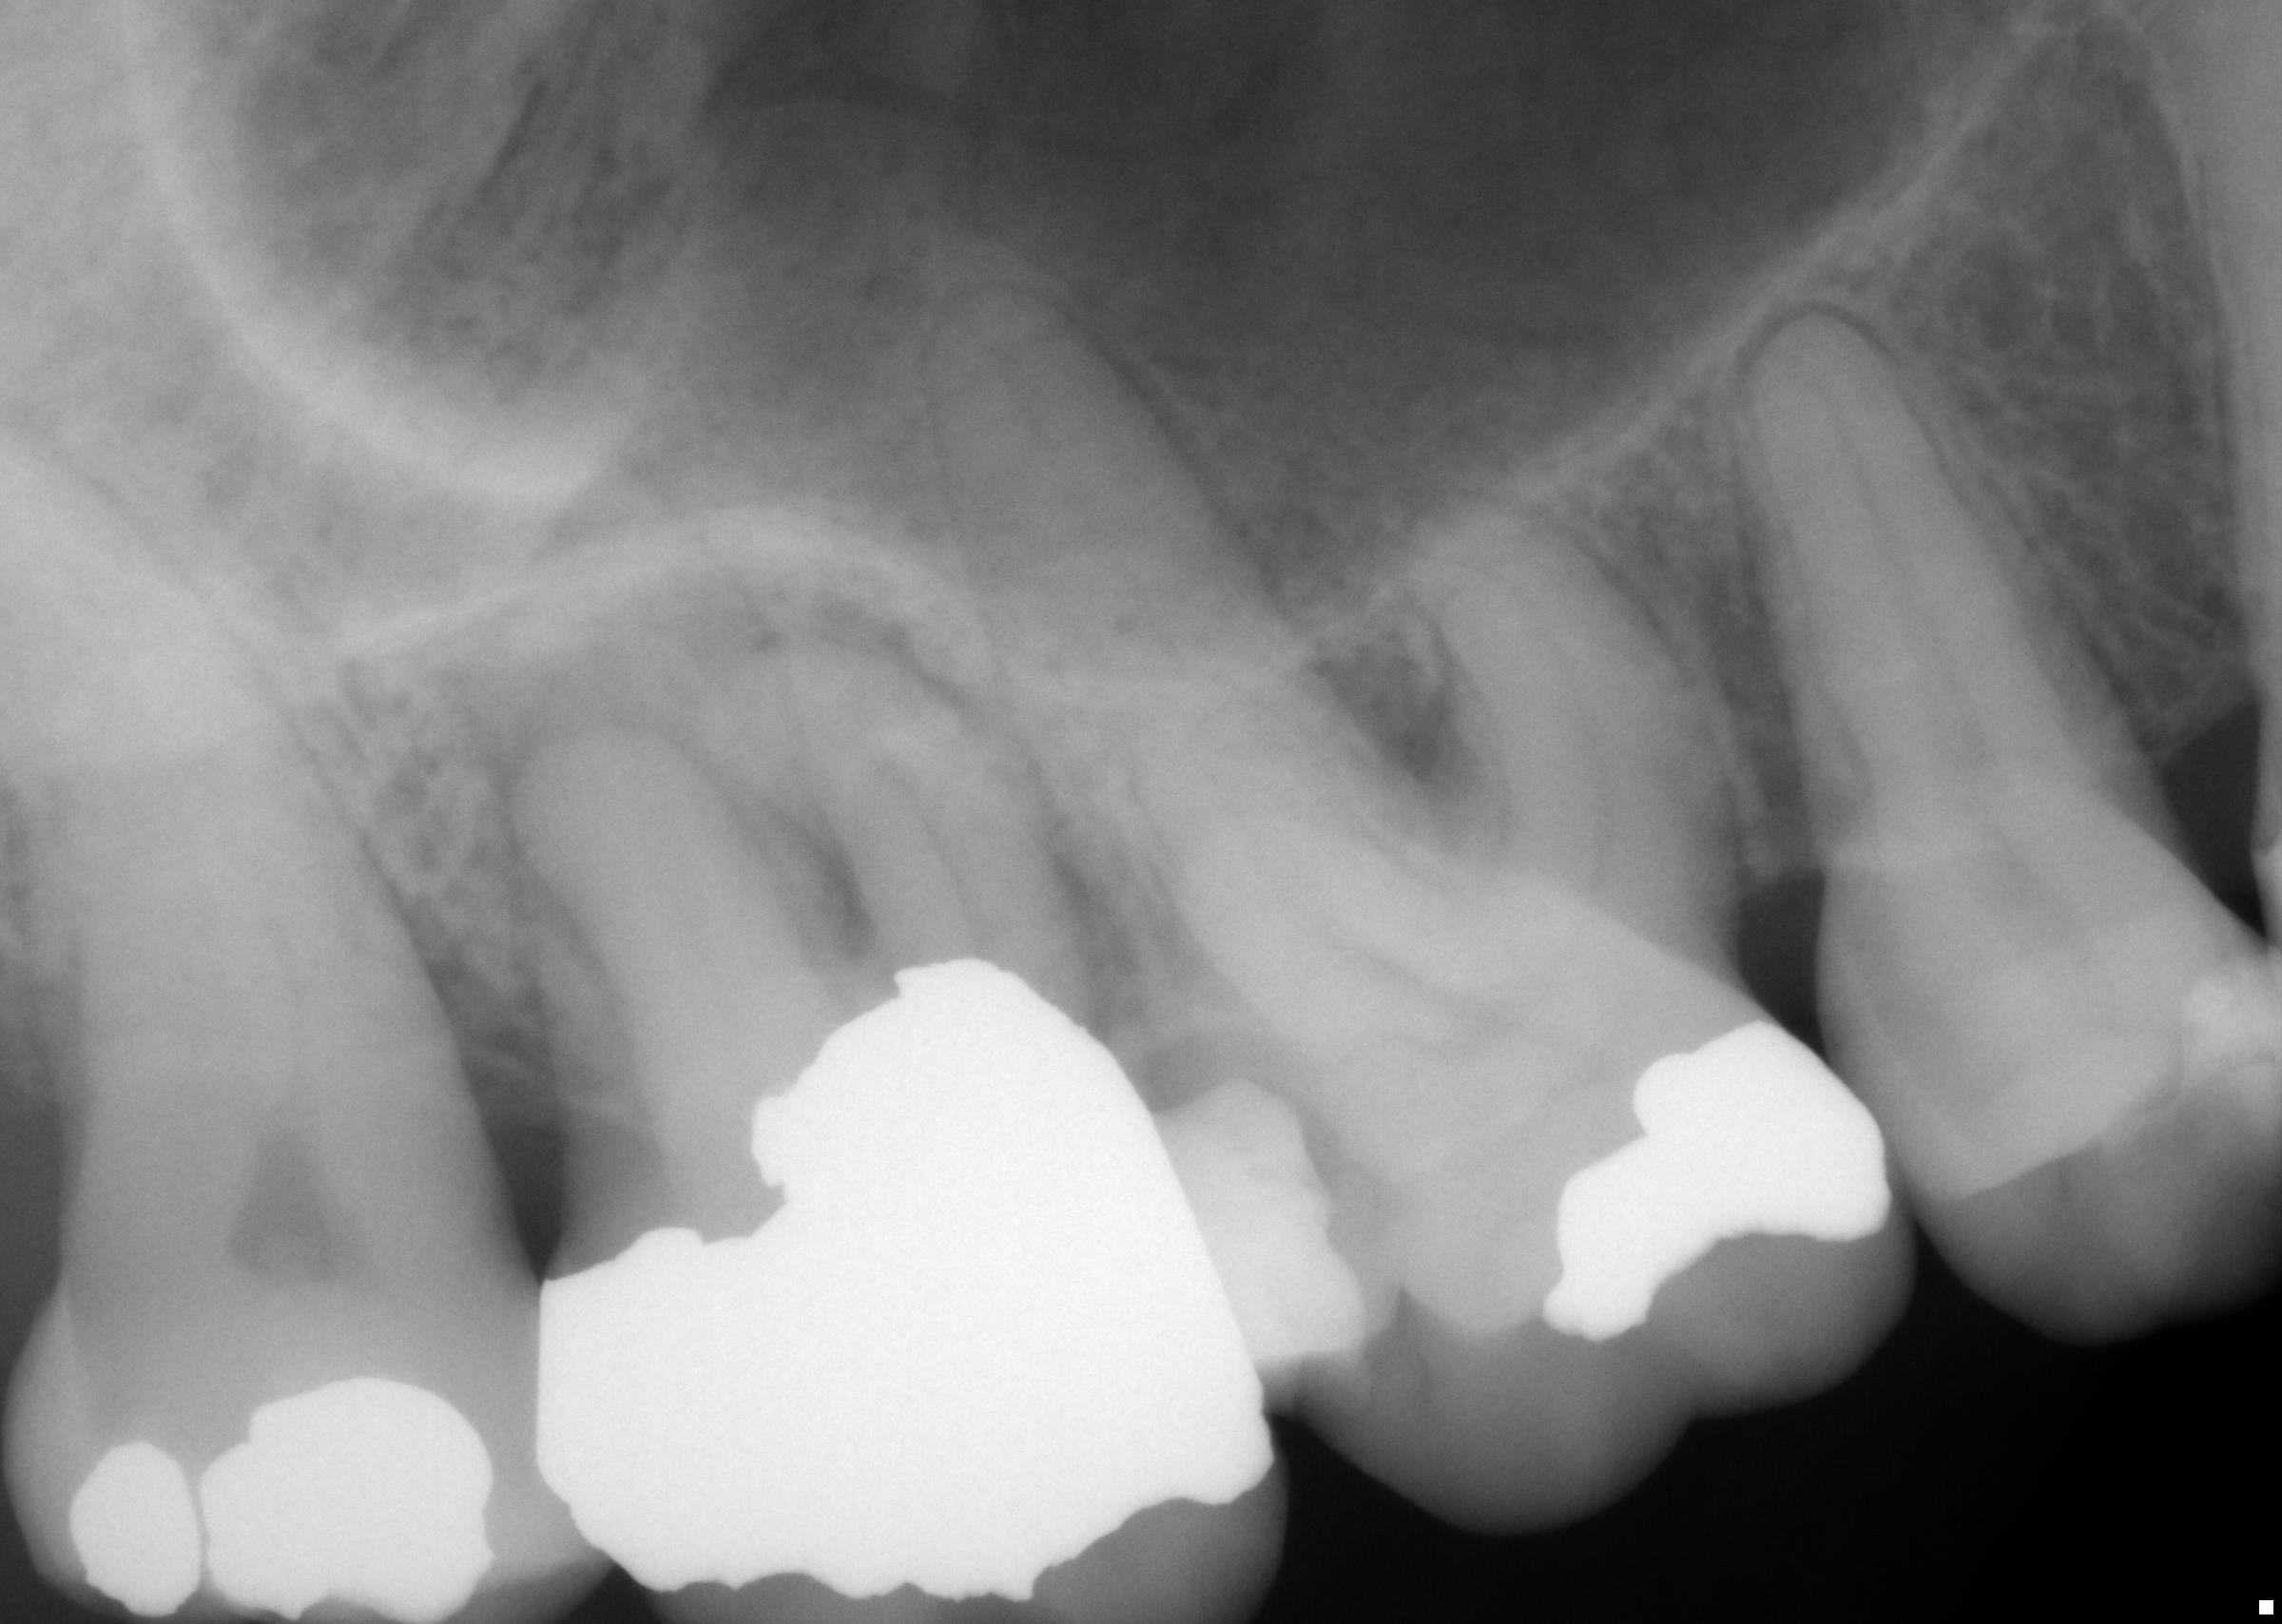

Retreatments What We Do Cornerstone Endodontics Cornerstone Endodontics Cornerstone endodontics offers root canals, endodontic retreatments, and apicoetomy in a comfortable and compassionate environment. Cornerstone endodontics is a specialty practice that offers root canal treatments and other endodontic services in a friendly and. Welcome to our meet the doctors page. We are an extension of your comprehensive dentist’s practice and will strive to make your visit here as comfortable. Cornerstone Endodontics.